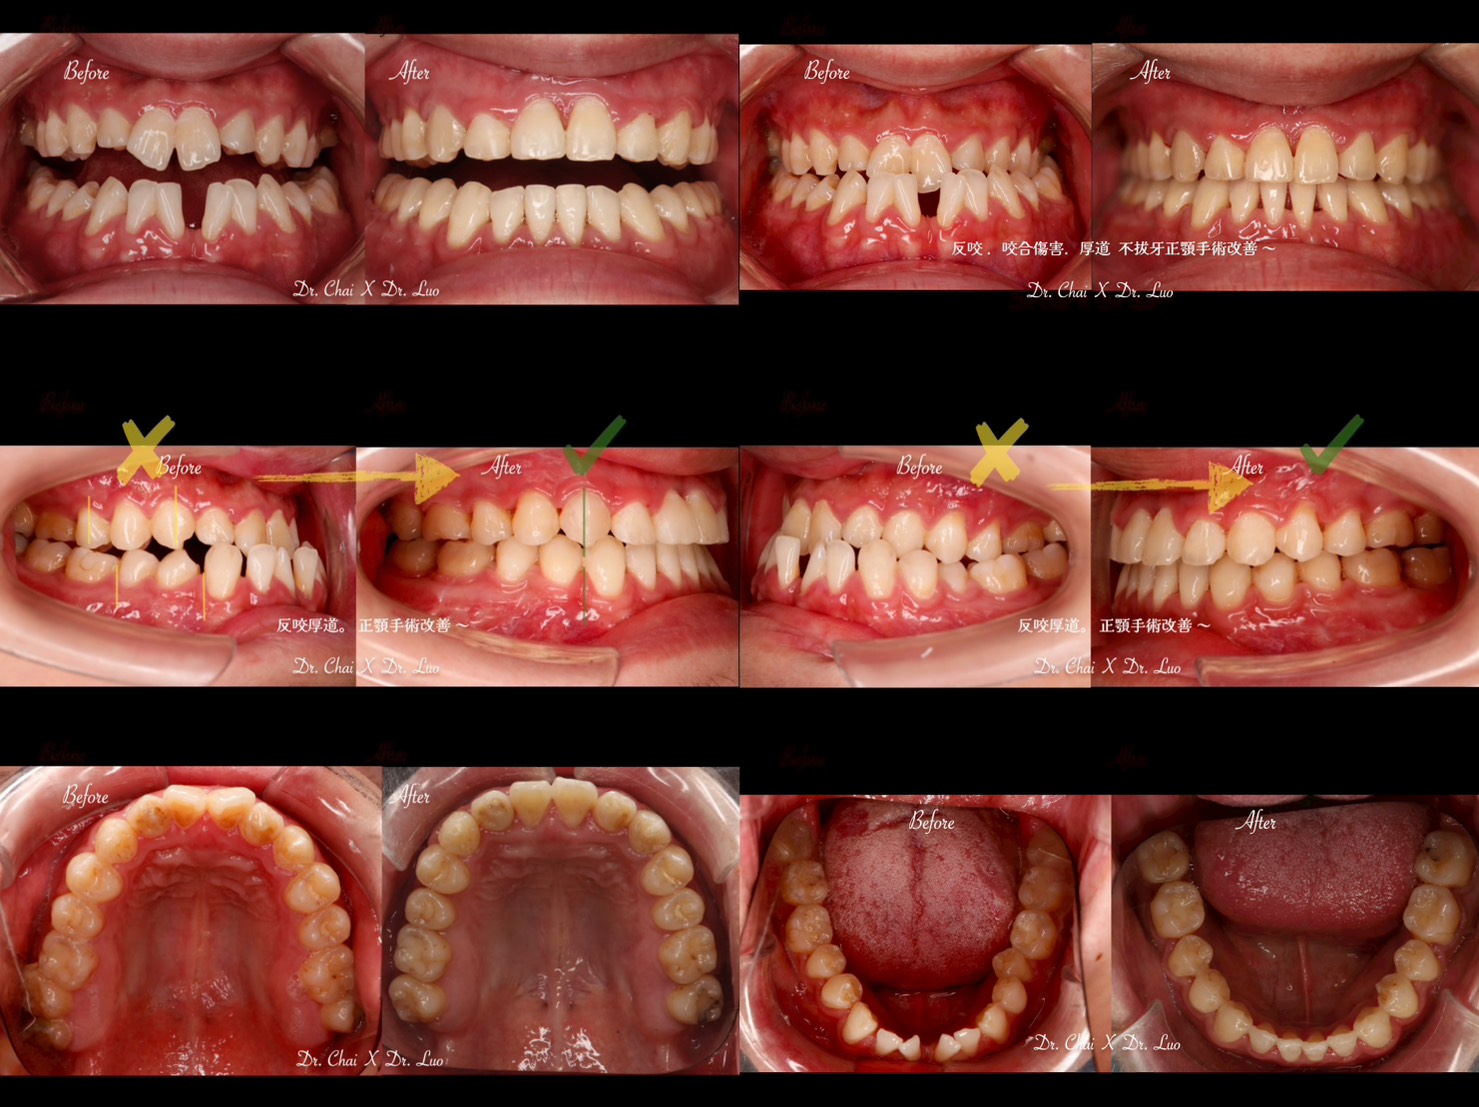

OGS combine ortho CASE (正顎合併矯正的案例)

翟聿飛醫師X羅文甫醫師

這次跟甫哥合作的案例真的是很有成就感!

很想跟大家說:OGS (正顎手術合併的矯正治療)其實不會可怕,也可以在骨骼基礎上做很完美的調整~

若有厚道. 後縮. 臉歪. 不對稱 等等骨性問題,不要害羞,趕緊來諮詢